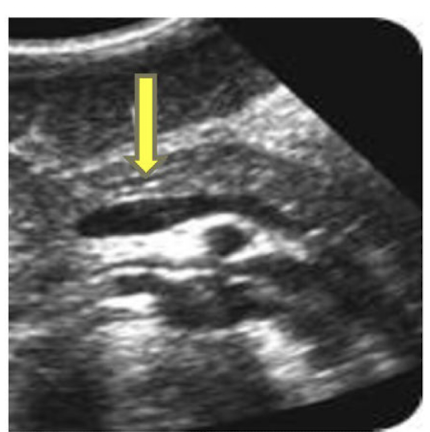

What is the yellow arrow pointing to?

Duct of Wirsung